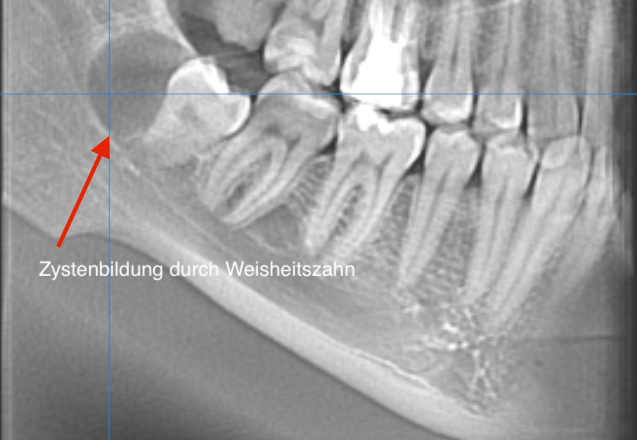

Operative Zahnentfernungen

Sie können notwendig werden bei tief beschädigten, kariösen Zähnen oder bei nicht durchgebrochenen, retinierten Zähnen, d.h. solchen, die noch unter dem Zahnfleisch im Knochen liegen. Meistens handelt es sich bei letzteren um Weisheitszähne, jedoch auch Eckzähne oder kleine Backenzähne können „retiniert“ bleiben. Ab dem 30. Lebensjahr kann jeder nicht durchgebrochene Zahn ein Entzündungsherd im Körper sein. Oft verursachen Weisheitszähne jedoch schon früher Beschwerden und müssen daher entfernt werden.

Verlagerte Weisheitszähne und entzündetes Kieferknochengewebe können auf den dreidimensionalen DVT-Aufnahmen genau untersucht werden.

Durch den Einsatz der Volumentopographie lässt sich die Anzahl und Ausrichtung der Wurzelkanäle sowie die Position und Ausdehnung von Tumoren und Zysten besser darstellen.